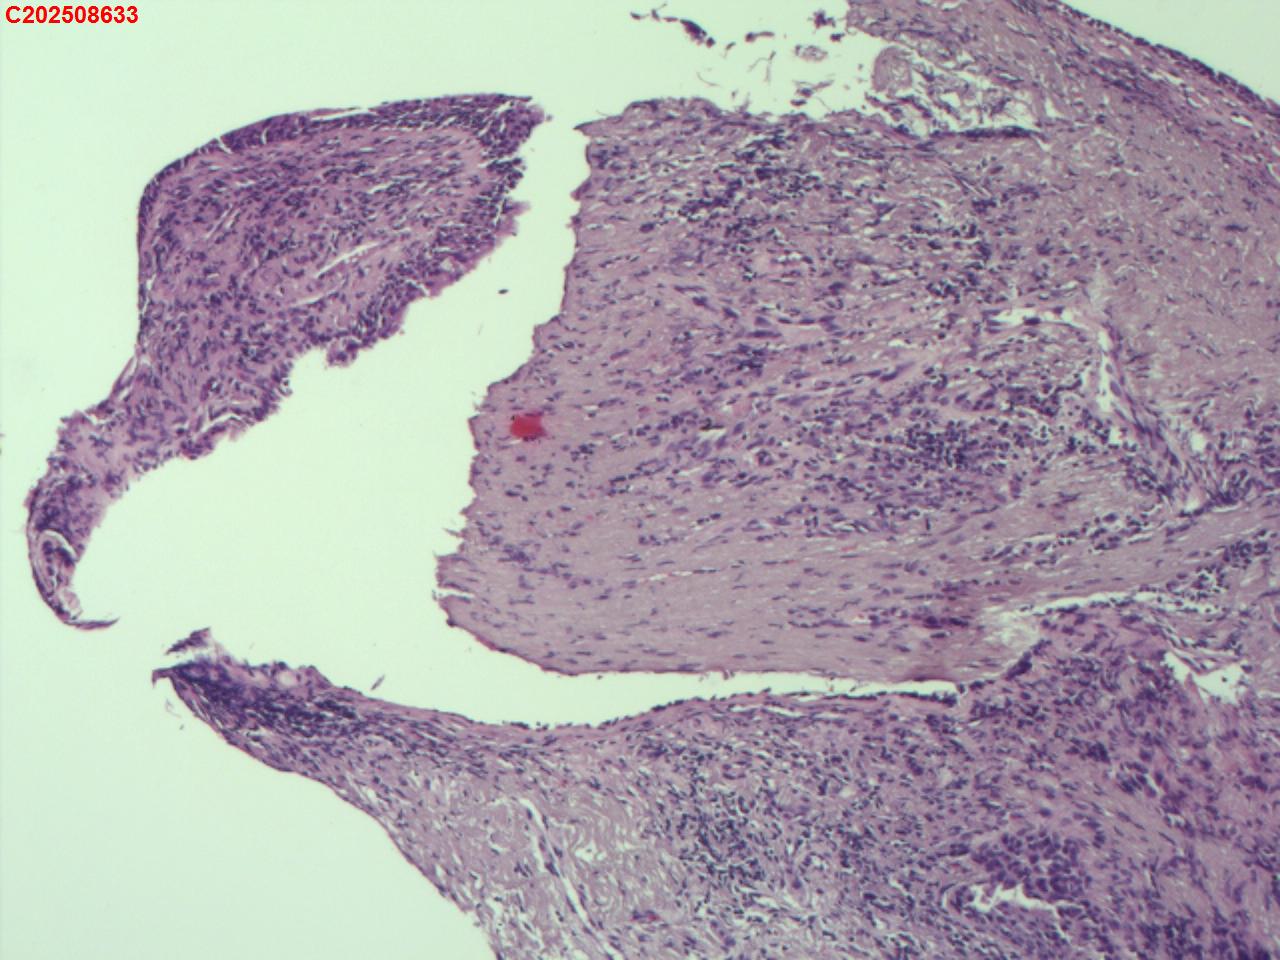

性别年龄82岁临床诊断肺结核?肿瘤?肺部感染?

大体所见2025-07-25 气管镜检查示:左侧主支气管、上叶、下叶及各段支气管未见异常。右侧主支气管未见异常。右侧中间段支气管可见碳沫沉积。右肺上叶前段支气管开口可见脓苔附着,支气管开口狭窄,内可见灰黑色新生物阻塞右肺上叶前段支气管管腔。2025-07-25结核感染T细胞检测阳性。2025-07-27肺泡灌洗液查结核分枝杆菌复合群阳性。

坏死物比较多,没有看到明确的肿瘤性病变,可以考虑给一个描述性诊断。